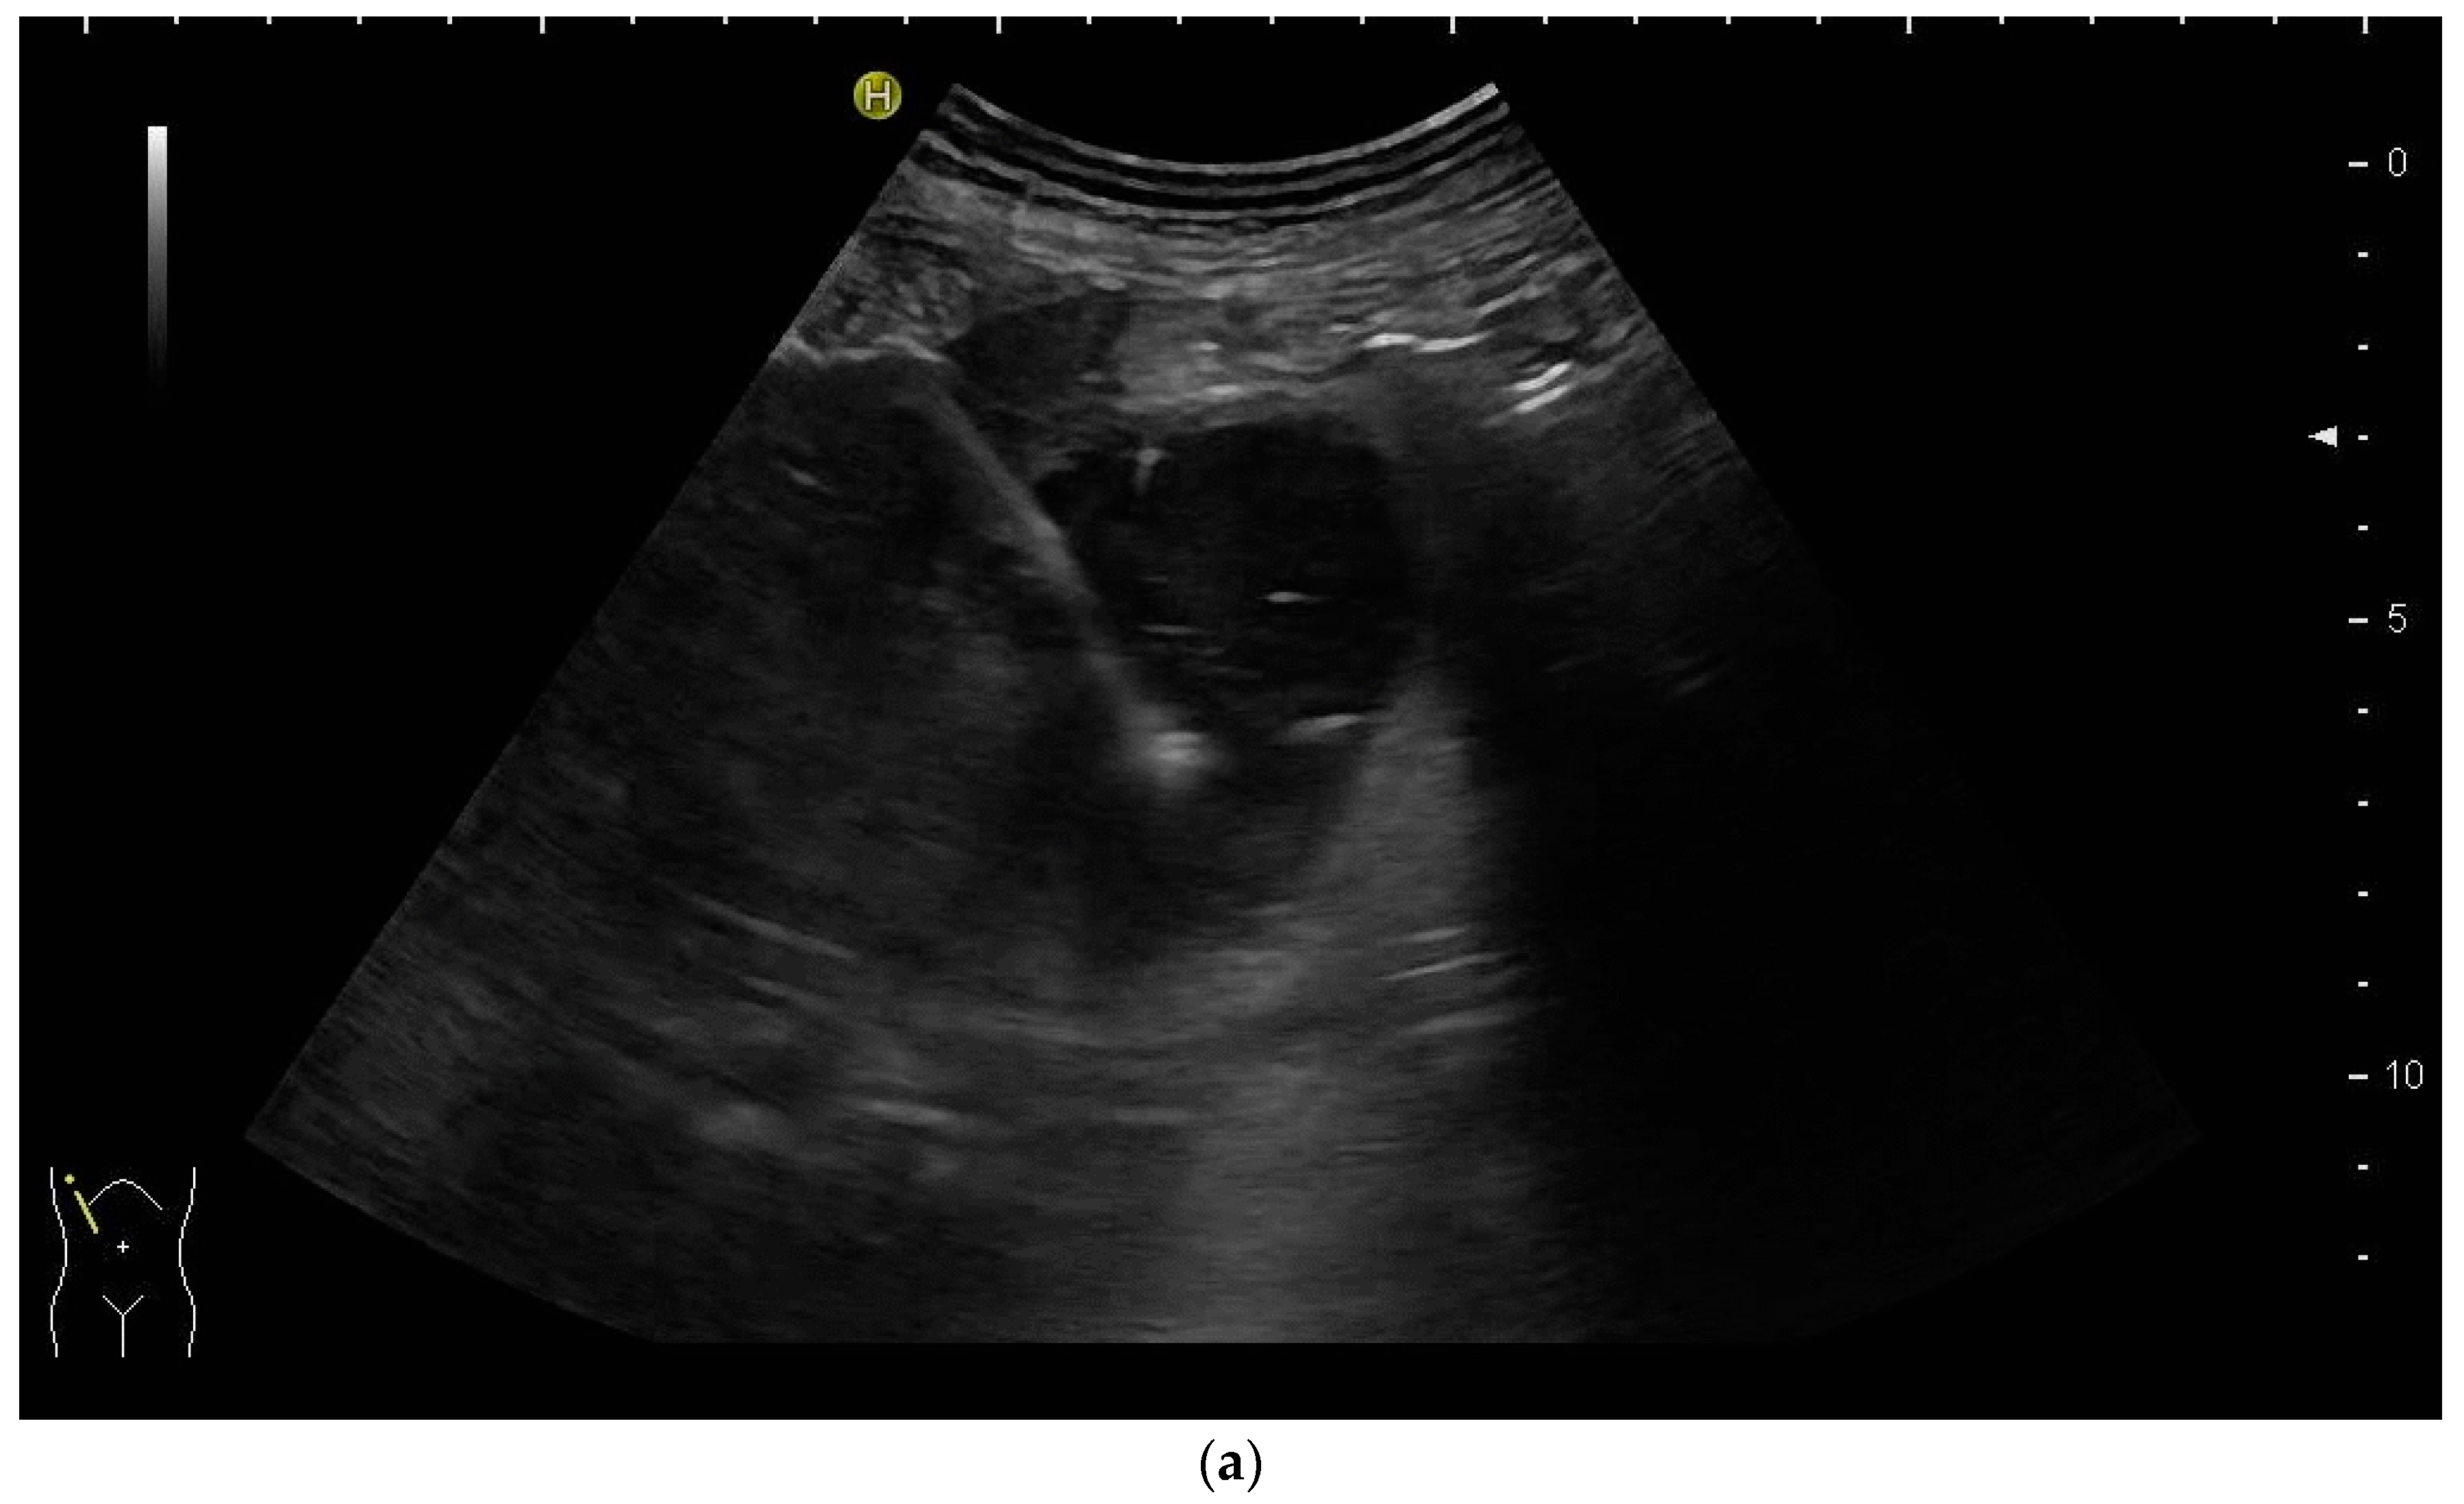

The aims of PGBD are the relief of symptoms and the disappearance of inflammation. If these criteria are met, the drainage can be removed. After pre-existing GB perforation, the integrity of the gallbladder wall should be documented. This can be performed very well by the injection of US-contrast agents (Figure 12 and Figure 13) [80].

After injection of one drop of SonoVue® diluted in 10 mL sodium chloride 0.9% via drainage, gallbladder perforation and leakage can be excluded. Only the drain and the gall bladder lumen show enhancement (left side: low-MI-mode, right side: conventional grey-scale image).

Gall bladder perforation. After injection of diluted US-contrast agent via the drain, contrast media appears at the lower liver surface. The drain was left in place for a few more days until surgery could be performed.

After the injection of one drop of SonoVue®, e.g., diluted in 10 mL sodium chloride 0.9% via the drain, gallbladder perforation and leakage can be excluded when only the drainage and the gall bladder lumen show enhancement, and no extravasation is observed.

Too early removal of the gallbladder drainage might cause the recurrence of cholecystitis. Leaving the drainage in place for too long might lead to persisting biliary leakage, as known from PTBD. Determining the perfect time for removal can be challenging.